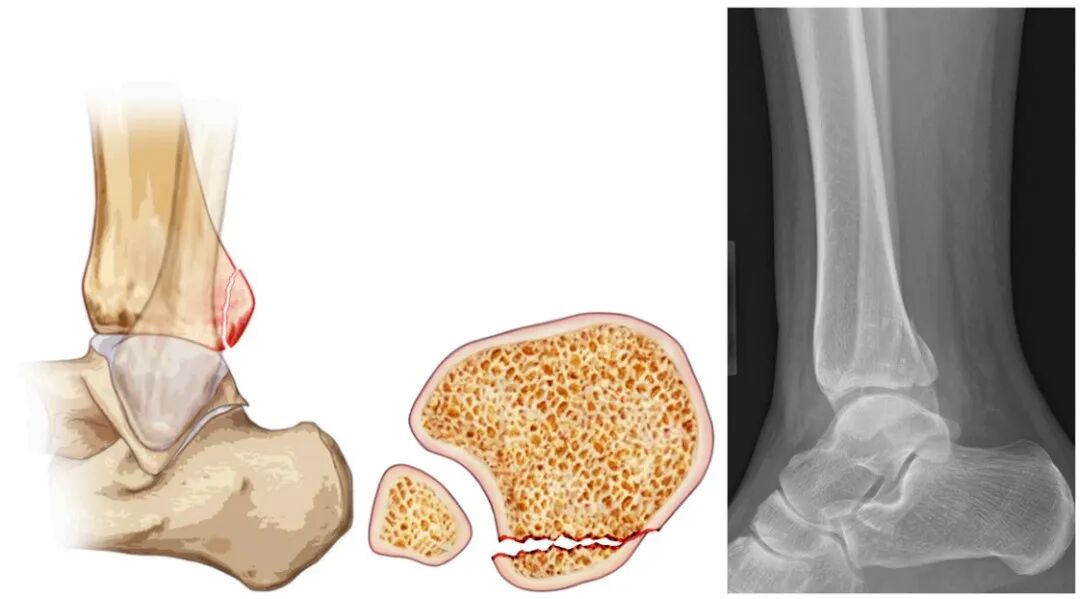

通常累及胫骨远端后侧边缘,多由踝关节旋转损伤(如旋后-外旋损伤)导致。骨折可能未明显延伸至胫骨远端后侧穹顶及踝关节负重面,在侧位X线片上表现为小型三角形骨折块,CT检查可能显示无关节受累或仅轻微受累。治疗方案取决于下胫腓联合复合体的稳定性,部分病例可能无需固定。

▲图示为后踝骨折,包含踝关节侧位视图、踝关节轴位视图,以及踝关节侧位影像。